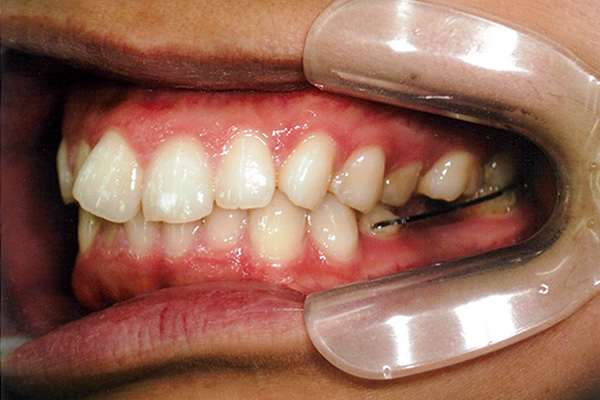

3ヶ月後